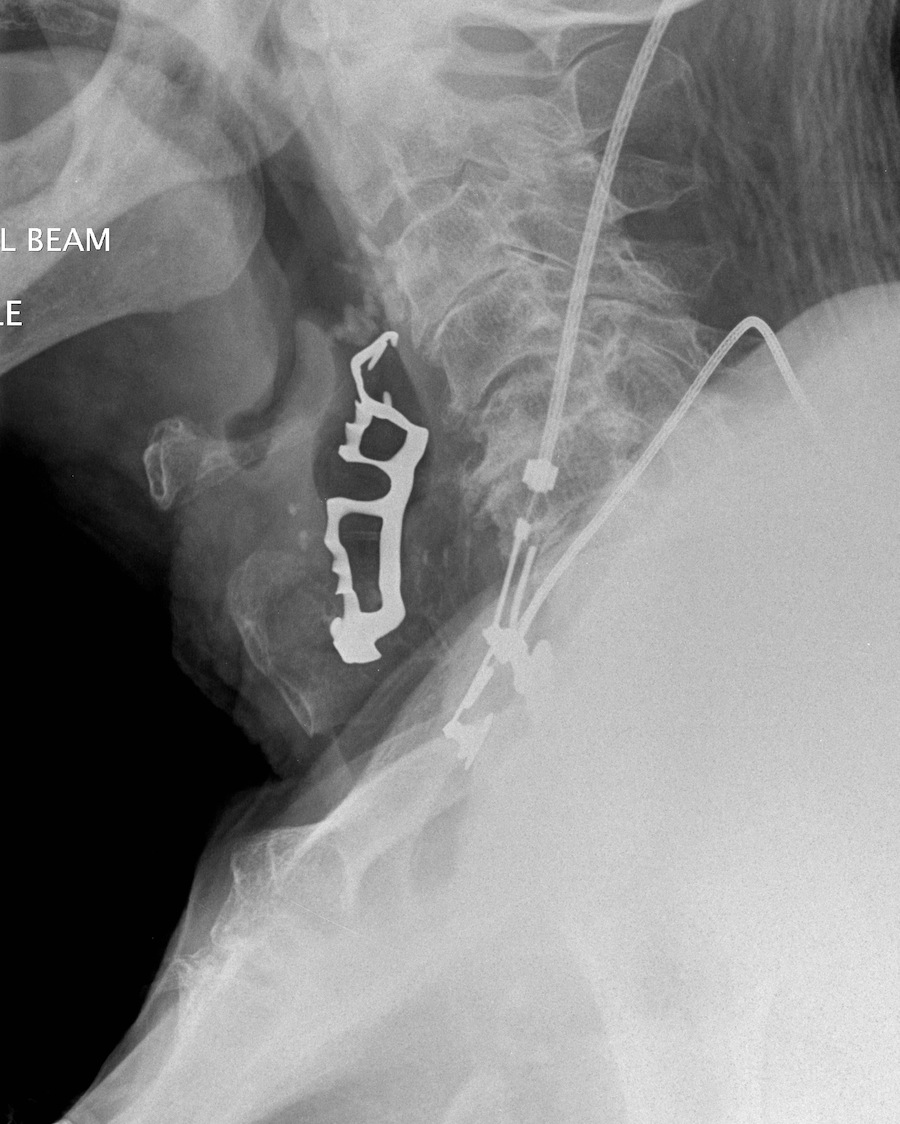

Dr. Na’ama Attar: What should you do if you swallow a …

10 month old baby swallows coin | Pediatric Surgery

Swallowed Battery, X-ray Photograph by Du Cane Medical …